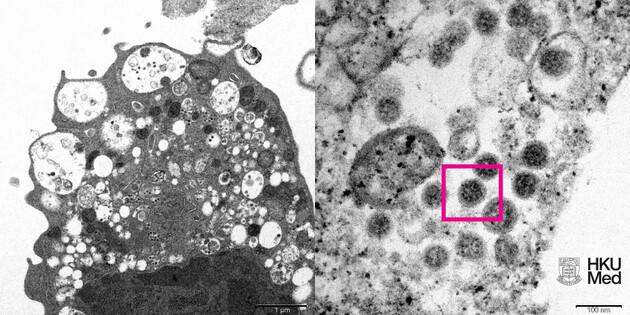

В мире был обнаружен первый случай смерти от нового штамма коронавируса.

"По прогнозам СНБО, эпидемическая ситуация в нашей стране на праздники должна быть стабильной. Ожидается, что новый штамм коронавируса "Омикрон" может появиться в Украине на этой неделе. Но результаты первых исследований в странах, где он уже обнаружен, свидетельствуют о более легком течении болезни", - отметил Данилов во время селекторного совещания под председательством президента Украины.